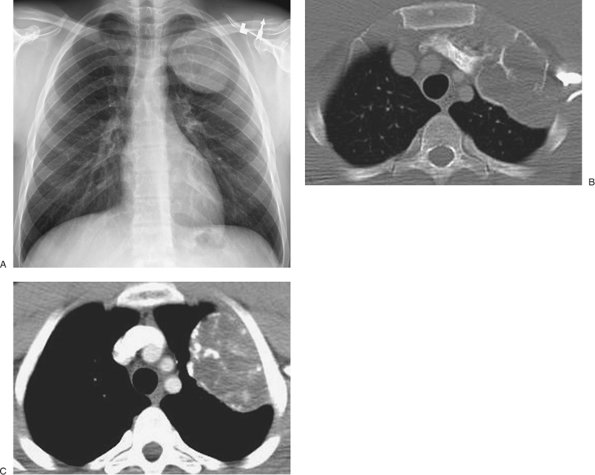

FIGURE 9-3. Subpleural squamous cell bronchogenic carcinoma. A: Posteroanterior (PA) chest radiograph of a 67-year-old woman shows a mass in the left upper hemithorax (arrows) that is contiguous with the pleural surface. B: CT with lung windowing shows the mass abutting the lateral pleural surface and major fissure. C: CT with mediastinal windowing shows that the mass is contiguous with the pleural surface. Centrally, the mass contains areas of low attenuation, consistent with necrosis.